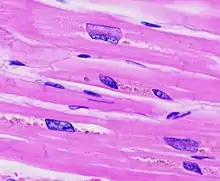

![]() | |

| The diagram shows a typical heart (left) and one with ventricular hypertrophy (right). | |